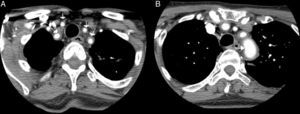

Angio-TAC: se confirma la presencia de un engrosamiento inflamatorio concéntrico/vasculitis de todos los troncos supraórticos (A) y del cayado aórtico (B) (flechas). La mayor afectación parece de la arteria subclavia izquierda, sin que se demuestren estenosis significativas a ningún nivel. En territorio carotídeo solo parece afectarse las carótidas comunes, sin extensión a ACI.

Caso clínicoMujer de 65 años, con antecedentes de asma bronquial, con bronquiectasias, APs con afectación mixta erosiva HLA-B27 negativo, tratada con metotrexato y leflunomida desde 2011 hasta 2013 por remisión. Acude por fiebre y astenia de 2 meses de evolución. No refería cefalea, alteraciones visuales, dolor toraco-abdominal ni en extremidades. En la exploración únicamente presentaba diferencia de presión arterial de 20mmHg y unos pulsos disminuidos en las extremidades izquierdas. Las arterias temporales no eran dolorosas a la palpación con pulso conservado y simétrico. En analítica se objetivó Hb de 9,9g/dl (12,0-15,0), velocidad de sedimentación globular 102mm/h (0-20), proteína C reactiva 140,90mg/l (< 5mg/l) e hierro 11 μg/dl (35,0-145,0). El resto de los parámetros fueron normales (TSH, CPK, Mantoux, marcadores tumorales, proteinograma, serologías, inmunología, sedimento orina y cultivos). La radiografía de tórax, el ecocardiograma, la gastroscopia con biopsia duodenal y la colonoscopia fueron normales. En la tomografía axial computarizada (TAC) toraco-abdominal se observaron bronquiectasias estables y un engrosamiento de la pared arterial de la aorta abdominal, indicativo de aortitis. Se amplió estudio con angio-TAC (fig. 1), que objetivó engrosamiento inflamatorio concéntrico de troncos supraórticos y cayado aórtico. Se realizó biopsia de la arteria temporal con confirmación histológica de ACG. Se inició tratamiento con corticoides a dosis de 2mg/kg/día en pauta descendente y metotrexato 15mg/semanal, quedando asintomática.